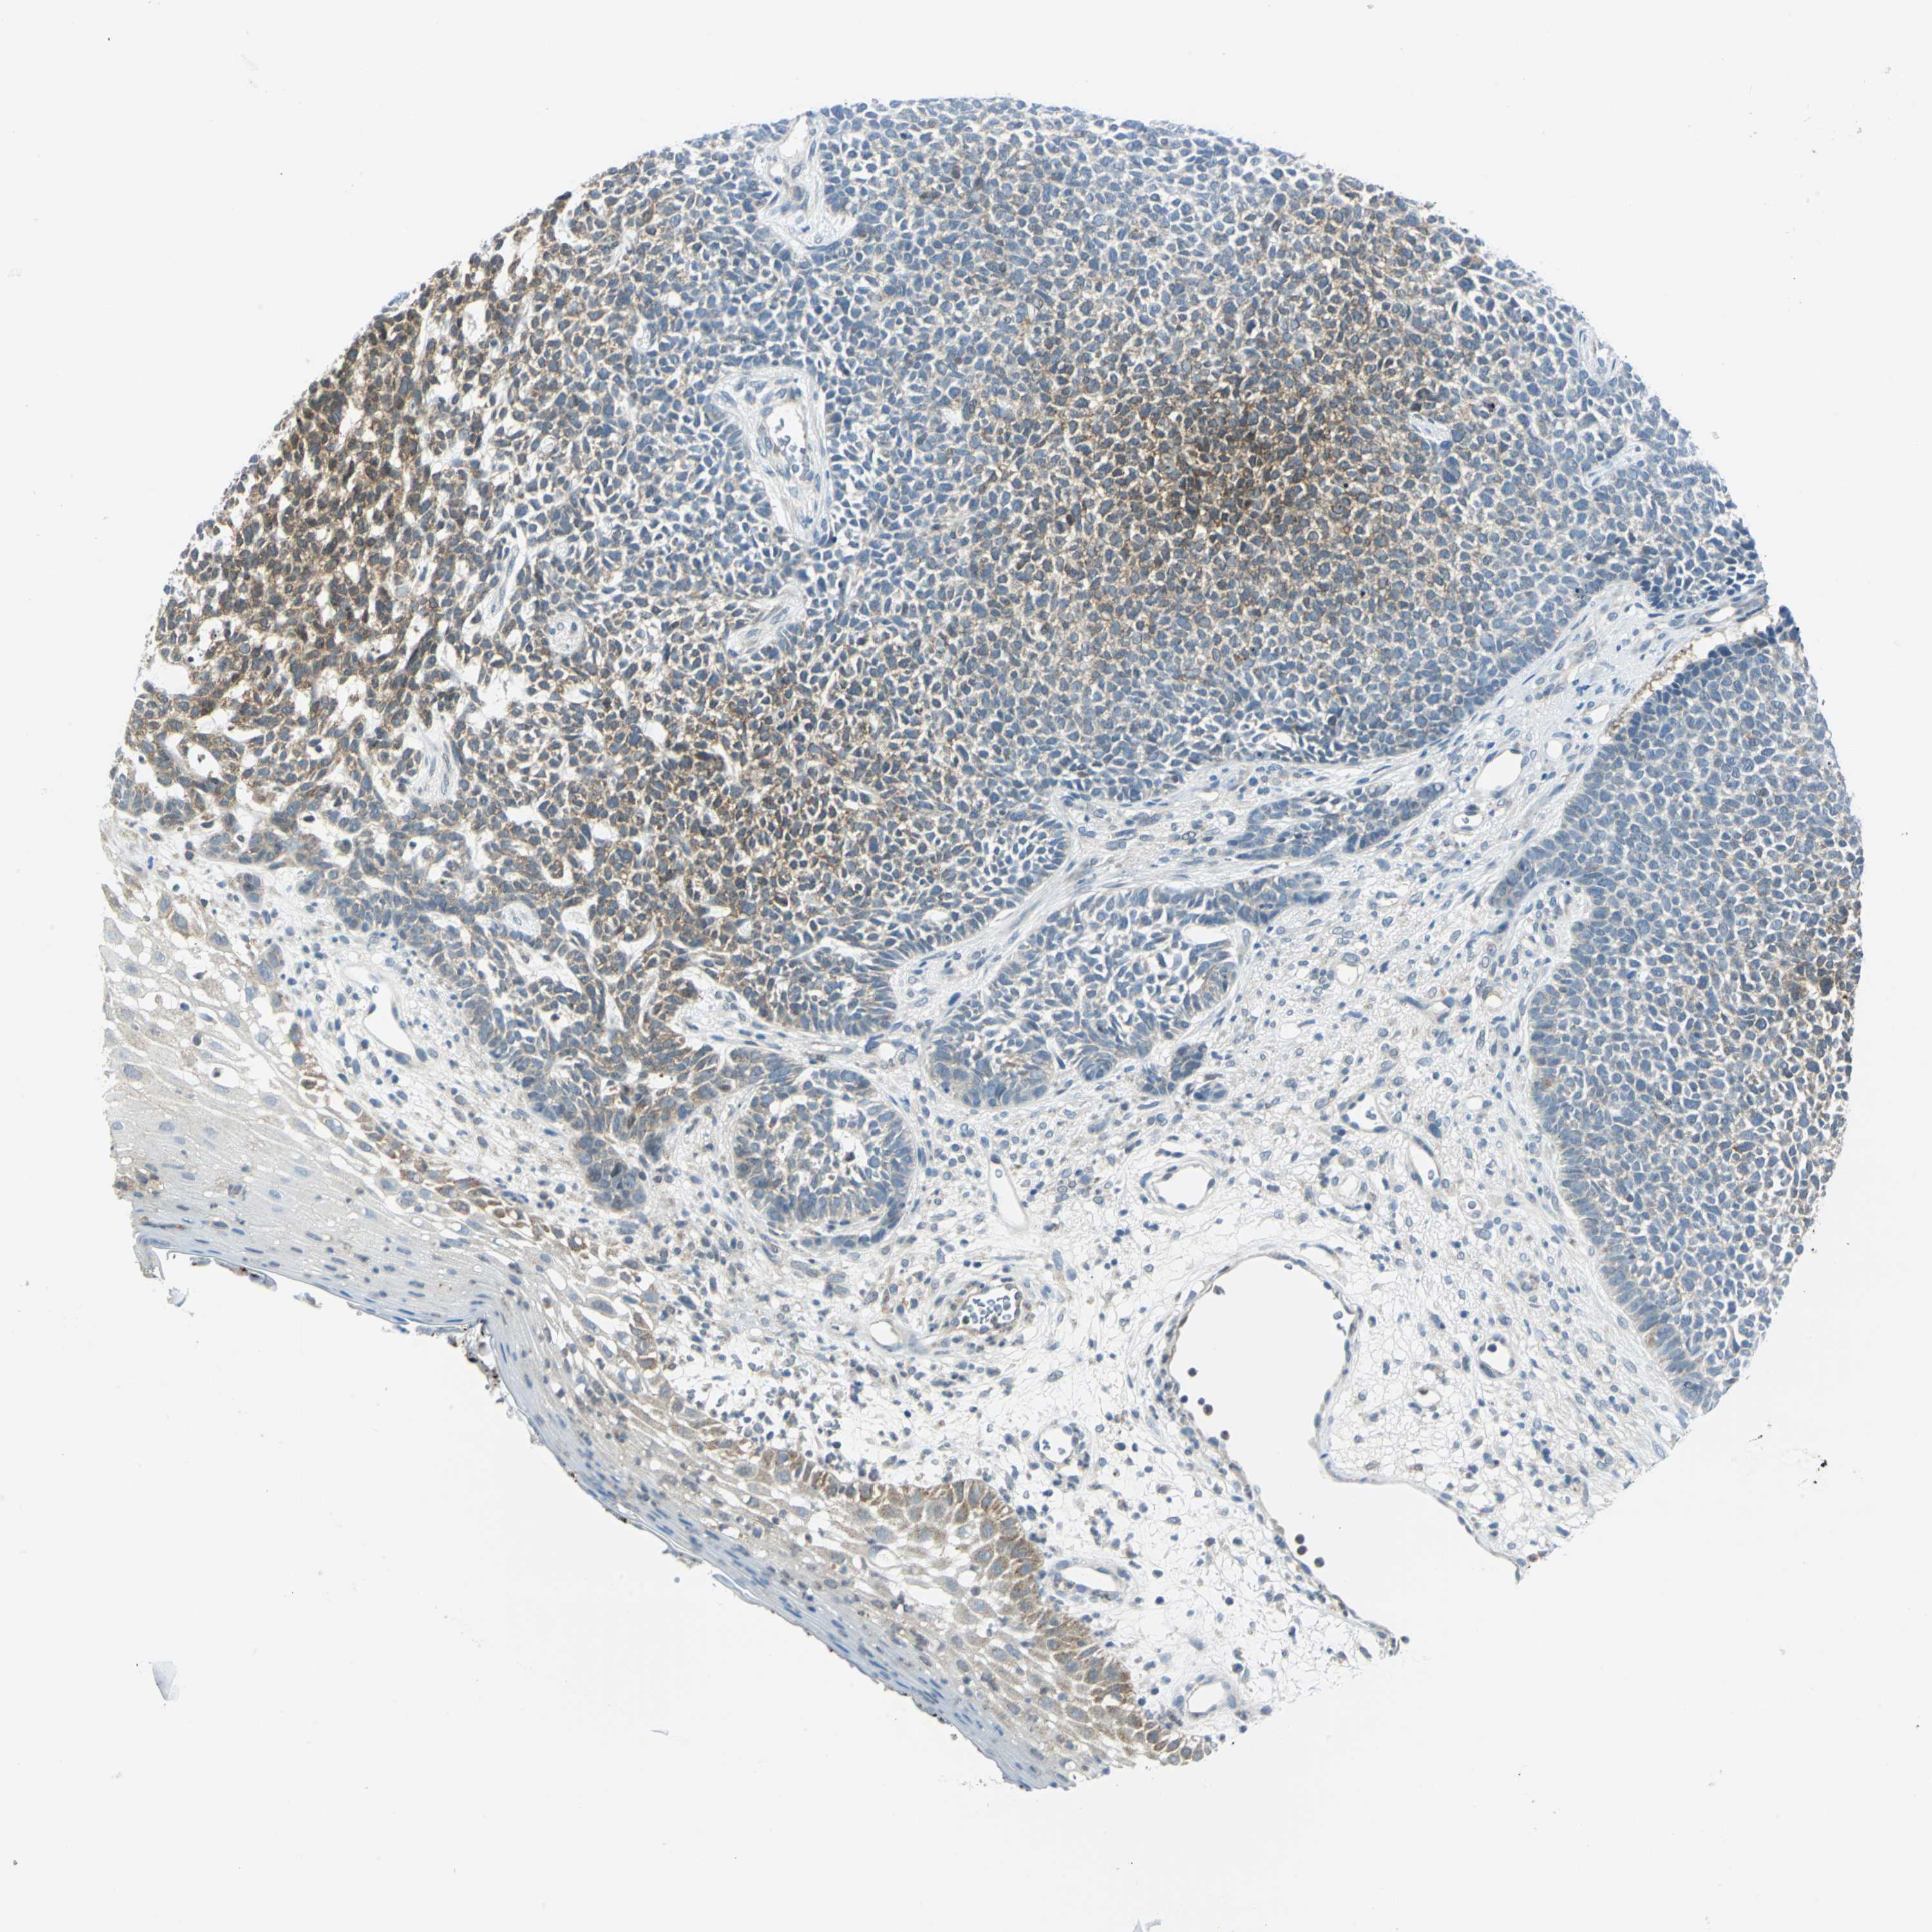

SKIN CANCER - Protein expressioni

A mouse-over function shows sample information and annotation data. Click on an image to view it in a full screen mode. Samples can be filtered based on level of antibody staining by selecting one or several of the following categories: high, medium, low and not detected. The assay and annotation is described here.

Each image is clickable and will lead to virtual microscopy that enables deeper exploration of all samples and also displays staining intensity scores, fraction scores and subcellular localization as well as patient and tissue information for each sample.

Antibody HPA004177

Staining

High

Medium

Low

Not detected

Intensity

Strong

Moderate

Weak

Negative

Quantity

>75%

75%-25%

<25%

None

Location

Nuclear

Cytoplasmic/membranous

Cytoplasmic/membranous,nuclear

Squamous cell carcinoma, NOS